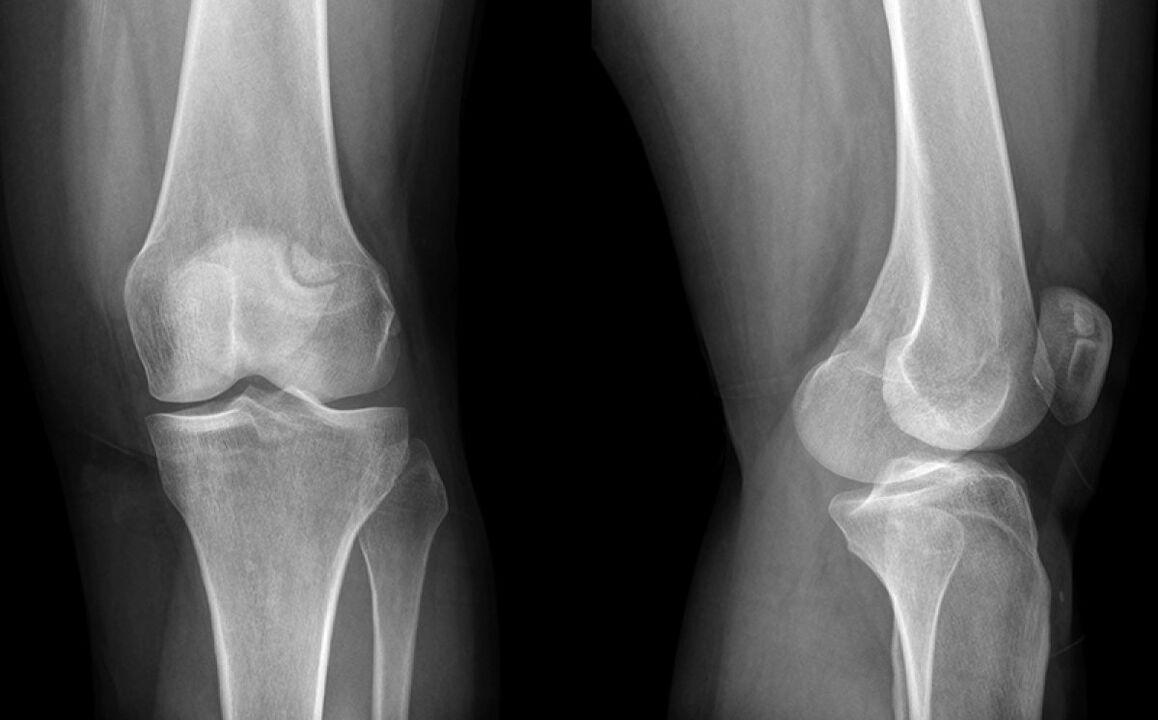

Das Knie verletzte drei Wochen. Letztendlich ging ich zu einem Arzt, der den Schaden an den Meniskus vermutete und zu einem X -Ray geschickt wurde. Die Diagnose ist das anfängliche Stadium der Arthrose des Kniegelenks.